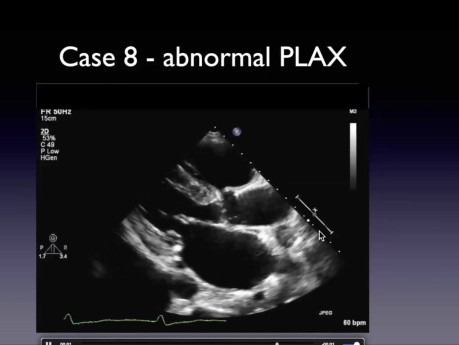

Zagadki echokardiograficzne – liczne przypadki

Prelegent: Howard Leong-Poi MD FRCPC, program director, Heart and Vascular Program, St. Michael's Hospital Professor in Medicine, University of Toronto. Cele: 1. Omówienie obrazów echokardiograficznych...